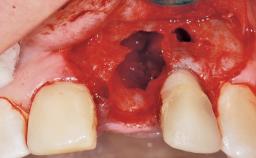

A 33-year-old female patient presented with an upper left central incisor that required extraction after a failed endodontic therapy. The tooth had been traumatized when the patient was a teenager and had undergone several endodontic treatments, including two apicectomy procedures. The patient was in good health and did not smoke. Clinical examination showed that the patient had a high lip line. In full smile, the gingival margins of the upper teeth were visible to the first molars. The gingival margins of central incisors 11 and 21 were only just showing. Examination of tooth 21 confirmed that the tooth was mobile and had hypererupted by 1 mm.

Placement Protocol Immediate implant placement

Socket Integrity Damage to one or more bone walls

Bone Volume Damage to one or more socket walls